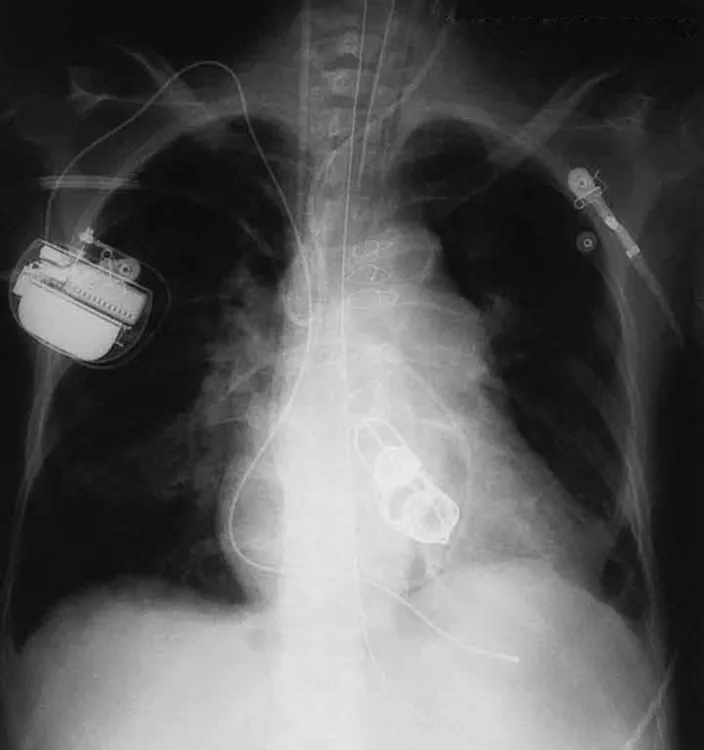

The ability of X-rays to penetrate matter depends on density, and so an X-ray image can reveal very detailed density information. Figure 24.20 shows an example of the simplest type of X-ray image, an X-ray shadow on film. The amount of information in a simple X-ray image is impressive, but more sophisticated techniques, such as CT scans, can reveal three-dimensional information with details smaller than a millimeter.

An X ray image of the chest is shown. It shows the section of the heart with artificial heart valves, a pacemaker, and the wires used to close the sternum.

Figure 24.20 This shadow X-ray image shows many interesting features, such as artificial heart valves, a pacemaker, and the wires used to close the sternum. (credit: P. P. Urone)